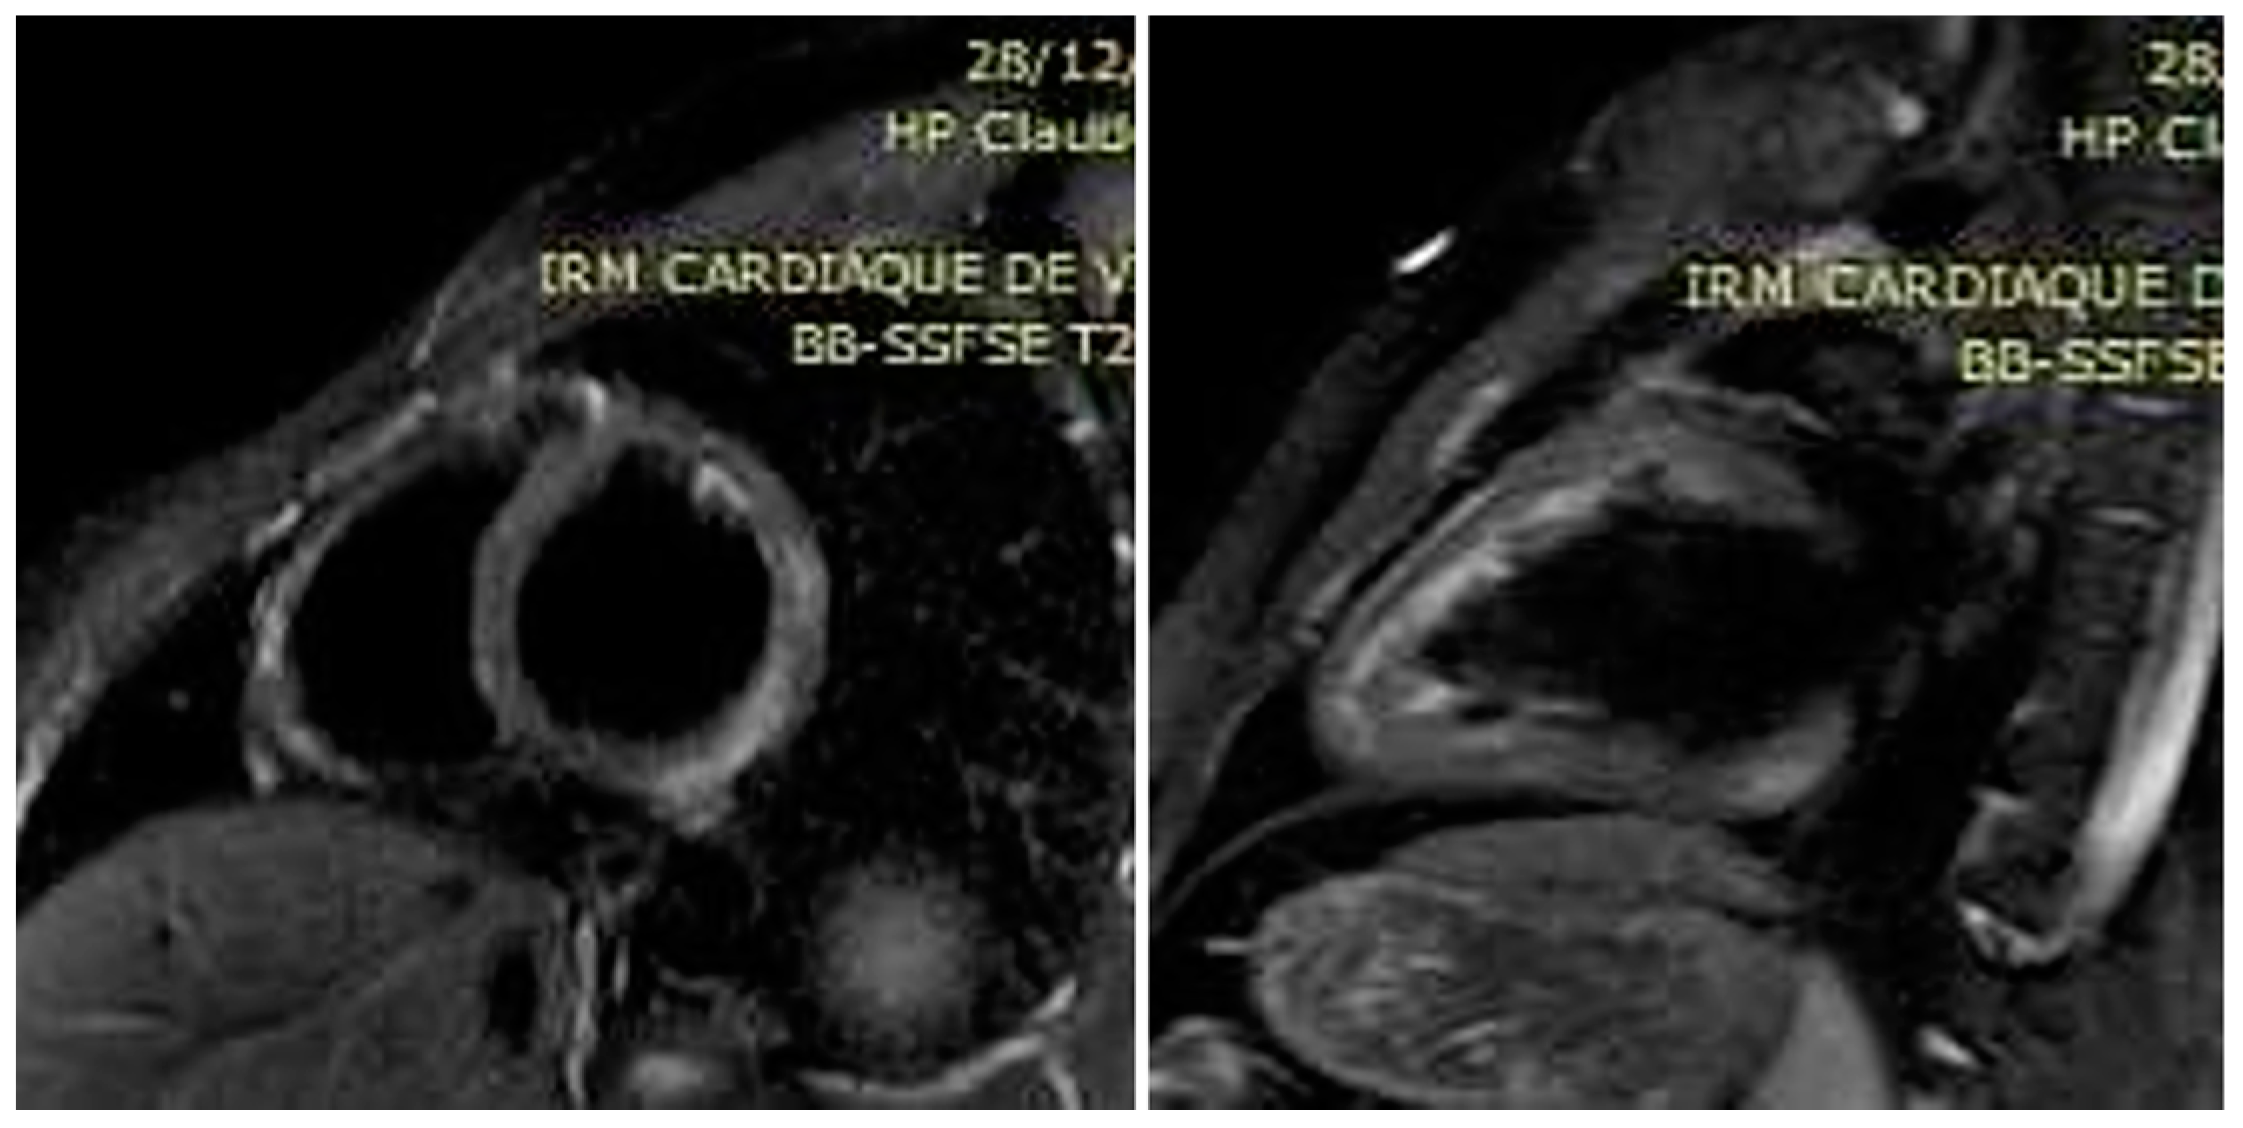

A 23-year-old male patient without past medical history presented to the emergency room with recent retrosternal chest tightness and pain. He reported recent gastro-intestinal (GI) symptoms of nausea, vomiting, 4-day watery diarrhea with transient episode of fever (38.7 °C). At admission, physical examination showed an impaired general status. He was afebrile (37.2 °C), respiratory rate 20 per min., cardiac assessment showed blood pressure of 140/70 mmHg, regular tachycardia of 100 beats per minute and normal cardiac murmur. Pulmonary examination showed a respiratory rate of 16 cycles per min, and auscultation was normal. He denied abdominal pain, and palpation showed no tenderness and no liver or spleen enlargement. He reported generalized myalgia but rheumatological evaluation did not show arthritis or productive myalgia. The electrocardiogram (ECG) showed left axis deviation with regular sinusal tachycardia. Routine laboratory showed leukocytosis 13 G/L (normal range < 10 G/L), neutrophilia 8.2 G/L (normal range 1.5–7 G/L) and lymphopenia 600/mm3 (normal range 1500 to 4000/mm3) on cell blood count, with elevated C-reactive protein of 130 mg/dL (normal range < 5 mg/dL), serum electrolytes, creatinine and liver enzymes within normal limits. Maximum Troponins and creatine kinase MB (CK-MB) were elevated to 678 ng/L (normal range < 14 ng/L) and 54 ng/mL (normal range < 7 ng/mL). The patient was admitted to the cardiac department for further workup. He was managed symptomatically with analgesics, anti-reflux and fluids. Transthoracic echocardiography (TTE) revealed a preserved ejection fraction (EF) of 55% with normal wall motions, no valvular dysfunction, normal pulmonary pressure and no pericardial effusion. His risk of coronary artery disease (CAD) was low; moreover, clinical, biological and echocardiographic presentation summed the hypothesis of an acute myocarditis. A large etiological workup, including repeated peripheral blood culture, Mycoplasma pneumoniae, Chlamydia pneumoniae, Coxiella burnetii, Borrelia burgdorferi, Leptospira spp., Rickettsia spp. and Brucella spp., was conducted. The serologies, such as urinary Legionella pneumophila antigen, were negative. Moreover, serologies of RNA viruses (coxsackieviruses A and B, hepatitis C virus, human immunodeficiency virus) and DNA viruses (adenoviruses, parvovirus B19, cytomegalovirus, human herpes virus-6, Epstein-Barr virus, varicella-zoster virus and herpes simplex virus) were negative. Autoimmune assessment, including antinuclear, anti-neutrophil cytoplasmic antibodies, systemic sclerosis and autoimmune myopathies specific antibodies and converting enzyme assay, were negative. The patient denied any recent drug intake. A Gram stain of specimen stool collected showed multiple curved and spiral Gram-negative rods. Biochemical tests indicated an oxidase, catalase and hippurate negative and indoxyl acetate-positive bacterial species, corresponding to C. jejuni. Stool cultures confirmed the diagnosis of C. jejuni sensitive to macrolides (Azithromycin/Roxithromycin/Clarythromycin) and flouroquinolones (Ciprofloxacin). Continuous telemetry monitoring showed some runs of non-sustained ventricular tachycardia (NSVT). Oral bisoprolol 2.5 mg twice daily was started for that, and oral 1 g of Azithromycin was administered. He remained clinically stable over the rest of the hospital course, and the diarrhea was progressively resolved. The patient remained stable, and we could perform cardiovascular magnetic resonance (CMR) imaging. Triple inversion-recovery black-blood T2-weighted STIR sequences showed focal areas of hypersignal in the subepicardium of the posterolateral left ventricular (LV) wall, indicative of myocardial edema (Figure 1). In addition, steady-state-free-precession (SSFP) cine CMR showed early hypersignal in the subepicardium of the posterolateral LV wall immediately after injection of 0.1 mM of Gadolinium chelates, indicating focal hyperemia (Figure 2). Inversion-recovery gradient-echo-based late Gadolinium enhancement techniques, acquired 10 min. after Gadolinium injection, revealed subepicardial nodular lesions of myocardial damage (Figure 3). The final diagnosis of C. jejuni-related acute myocarditis was supported by the Lake Louise criteria [7]. The patient was discharged free of symptoms after one week in hospital. On close follow-up, his C-reactive protein and cardiac enzymes normalized after three weeks. Repeated TTE and 24-h ECG were normal, so bisoprolol was progressively discontinued after 6 months. Control CMR imaging at 3 months showed regression of the focal areas of hyper signal in the sub epicardium of the posterolateral left ventricular (LV) wall.

Figure 2. End-systolic image extracted from SSFP cine CMR in the basal LV short-axis view, showing early hypersignal in the subepicardium of the posterolateral wall shortly after (1 min.) injection of 0.1 mM of Gadolinium chelates, indicating focal hyperemia (arrows).